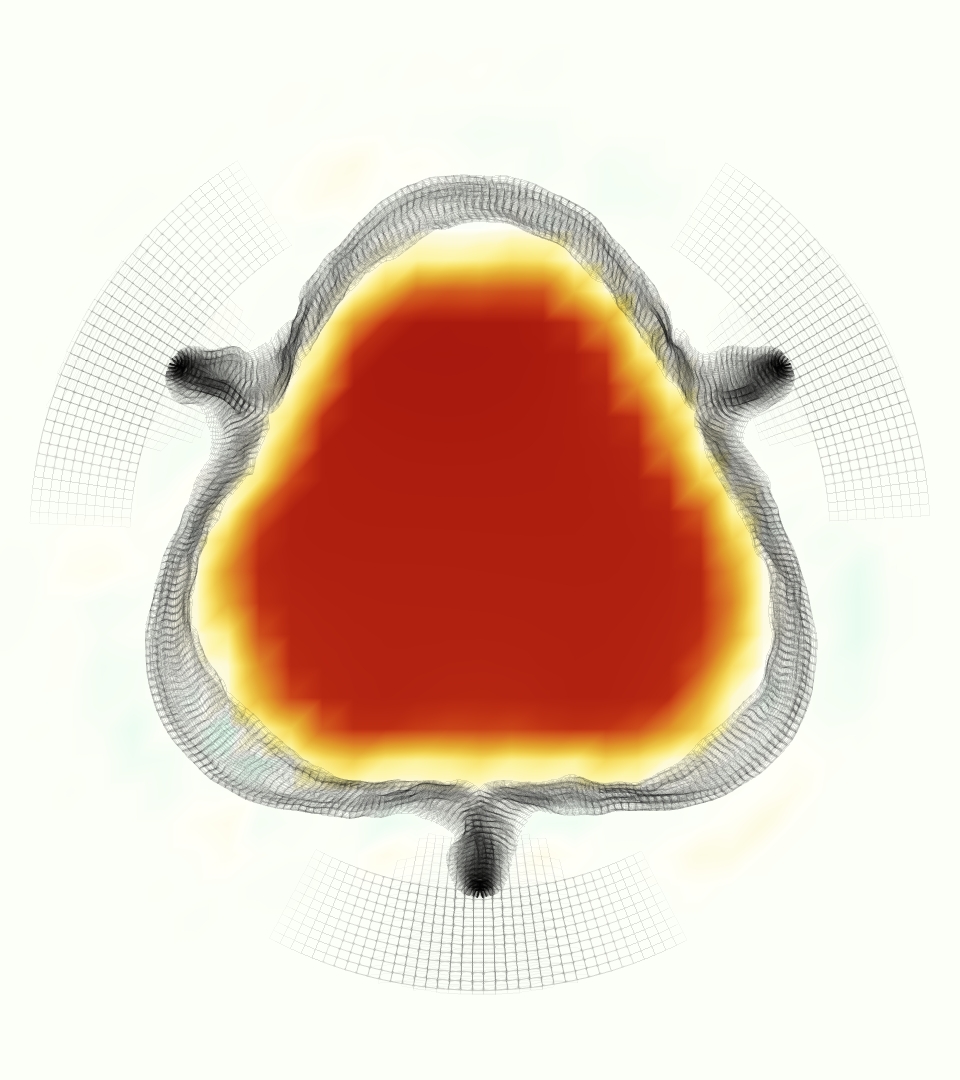

The gross morphology of the model valve that emerged from this process is shown in Figure 4. The free edge was 2.87 cm, corresponding to 3.3 cm in the predicted loaded configuration. After the pinching the leaflets together at the commissures, this left approximately 2.1 cm of free edge rest length per leaflet free to move independently of the other leaflets, within measurement error of ±0.1 cm from the free edge length of 2.2 cm measured on the prostheses. The leaflet rest height was 0.94 cm corresponding to a predicted loaded height of 1.44 cm. The measured leaflet height of 1.3 cm is nearly the predicted loaded height of 1.44 cm, which may be because the leaflets are so compliant in the radial direction, that pulling them flat to measure them achieved substantial stretches. The fiber orientation of the model runs from commissure to commissure and qualitatively matches experimental observations [38], though direct quantitative comparison is beyond the scope of this work. One minor limitation is that we do not add bending rigidity to the leaflets, beyond what emerges from the thickening process described above, and thus may not accurately capture leaflet flutter or other similar behaviors. Based on the thickness of mm, we estimated the mean tangent modulus at the predicted loaded stretches as dynes/cm2 circumferentially and dynes/cm2 radially. The prosthetic valve tissue is fixed in glutaraldehyde, and literature values for the fully-recruited circumferential tangent modulus of fixed porcine aortic valve tissue vary widely. Based on the experimental measurements of Billiar and Sacks and their constitutive law for valves fixed under 4 mmHg of pressure, we evaluated their constitutive law at the relevant stretches and and estimated the circumferential tangent modulus to be dynes/cm2 [6]. Rousseau et al. reported moduli ranging from to dynes/cm2, depending on the applied preload during fixation [36]. Sung et al. reported moduli ranging from to dynes/cm2, depending on fixation pressure [43]. Thus our estimated tangent modulus falls within the range of existing studies, so we considered our resultant modulus in good agreement given the complexity of the steps involved, phenomenological nature of the constitutive law and uncertainties in experiments. We do not have access to the precise material properties of the prosthetic valve, and further, the only literature we could find on the material properties of a similar prostheses reported the tangent modulus at one particular loading, which did not appear to be at a relevant stretch for comparisons with our model [19]. Thus, our model has material properties in a reasonable range for a fixed aortic valve prostheses (placed in the pulmonary position in our simulations), but it does not directly model the material properties of the prostheses.

We constructed the model vessel for FSI simulations from data from the MRI scans (Figure 4). The signal magnitude of 3D printed model material is distinct from the signal of the fluid in the scans, and we applied a thresholding operation to generate a three-dimensional model of the printed vessel surface. Using the MRI data ensured that the MRI and simulation coordinates were consistent in space and there were no alignment or registration errors. While using the files that generated the 3D printed model would have offered more spatial fidelity, the potential error in flow fields due to any mis-registration would have likely been much more substantial. Using Meshmixer (San Rafael, CA), we smoothed the mesh to remove stair-step effects and removed artifacts from the valve scaffold. We then remeshed to the desired edge length of 0.25 mm and extruded the model 0.25 mm and 0.5 mm to create a three-layer structure. As in the valve, this serves to eliminate the “grid aligned artifact” that can occur with pressure differences across thin membranes in the IB method [16]. Flow extenders of length 1 cm were added to the vessel at the inlet and both outlets to ensure that the normal to the vessel was aligned with the normal of the fluid box at the inlets and outlets. In FSI simulations, the vessel was held in place using target points, stiff springs of zero rest length that connect the current position of each model node to its desired position (Section 3.3). Additional linear springs are placed on each edge in the triangulated model. These springs are not meant to model a particular material and only serve to keep the vessel rigid and stationary throughout the simulation.

The emergent hemodynamics showed excellent qualitative agreement with experiments. Slice views of the axial component of fluid velocity ( component) in the sagittal plane that cuts through the center of the vessel, parallel to the flow direction, are shown in Figure 5. The flow in both the simulation and the experiment began to accelerate at the same time, with a jet forming through the open valve leaflets. The velocity, angle, and shape of the jet agreed well between the two cases during systole. The simulation captured the slight upward angle of the jet, which was not fully centered in the vessel. It also matched the location where the jet impacts the wall and the slower speed of the jet as it turns with the MPA downstream. As the flow decelerated, the fluid along the interior curve of the vessel reversed first while forward flow persisted where the jet was strongest, as seen in both the simulation and experimental results.

In both the experiment and the simulation, a separation region of reverse flow developed along the interior curve of the vessel under the core jet through the valve. The reverse flow began to develop at the same time in the cardiac cycle and grows throughout systole. The simulation lacked reversed flow in the entire region where reversed flow was present in the experiment, but this region developed some flow separation and had much slower flow than elsewhere in the vessel. Thus, the simulation captured that this is a distinct region from the core jet through the valve opening. There was a smaller amount of slower and slightly reversed flow along the outer curve of the vessel, close to the valve annulus and scaffold support. This region was well-matched between the experiment and the simulation.

Slice views of the (axial) component of fluid velocity in the axial plane, orthogonal to the flow direction, show that the simulation replicated the development of the jet over the cardiac cycle. At each phase, the simulation matched the forward speed of the core of the jet and the locations of reverse flow back towards the valve annulus. While there are some differences in the shape of the jet at certain phases and locations, the simulation clearly produced the general dynamics of the cardiac cycle that are seen in the experiment.

At = 0, the axial slice directly at the valve annulus shown in columns 1 and 2 in Figure 6, there was excellent agreement between the simulation and experiment over the cardiac cycle in the speed and shape of the jet through the valve. In both cases, the axial velocity increased as the flow accelerated during systole and the valve leaflets opened, then decreased during diastole with slight negative velocity before the valve leaflets were fully closed. The forward flow through the valve annulus did not form a full circle, but rather developed a triangular shape with a point of the triangle forming along the interior curve of the vessel, at the bottom of the axial slices. At = 0, the points of this triangular jet shape aligned with the commissures of the valve. This shape persisted during peak systole and was well-matched by the simulation.

The axial slice = 0.625 cm, shown in columns 3 and 4 in Figure 6, cut through the support scaffolding of the valve and the leaflets when they are open. In the experimental data, the shape of the jet changed as it moved downstream. A triangular shape occurred, but the points were then aligned with the middle of each open leaflet as opposed to the commissures. Those points were also more rounded than they were at = 0. The peak velocity of the jet was faster at = 0.625 cm than at = 0, as the flow accelerated through the open valve leaflets. The simulation produced these features at = 0.625 cm. The triangular shape of the jet shifted similarly, and its speed increased compared to the upstream slice. As the flow decelerated into diastole, the jet shape remained roughly triangular but diminished in intensity before disappearing after valve closure.

The jet continued to develop at = 1.25 cm, an axial slice immediately downstream of the valve scaffolding and open leaflets, shown in columns 5 and 6 in Figure 6. In the experimental data, the points of the triangular jet shape extended further towards the vessel wall. In addition, regions of reversed flow developed in the locations downstream of the commissures, resulting in curved sides to the shape of the jet. Each tip of the jet was unique, due to variations in the individual leaflets in the physical bioprosthetic valve. These variations are apparent in the velocity fields, possibly because the jet edges are similar enough cycle to cycle that irregularities are still being captured even with phase averaging. Further discussion of these features can be found in Schiavone et al. [39], which showed that the jet tip shapes occurred in different pulmonary anatomies, demonstrating that they were likely due to inherent properties of each leaflet. The leaflets in the mathematical model of the valve are identical, so these nuances in leaflet variation could not be replicated. The simulation did capture some of the extension of the tips of the jet, as they were closer to vessel wall at slice = 1.25 cm than = 0.625 cm. The curves in the triangular sides of the jet were also present in the simulation, though they were less pronounced than the experimental data. At both = 0.625 cm and = 1.25 cm, the jet shape in the simulation was smoother than the jet in experiment. It is possible that the free edges of the leaflets in the mathematical model are not fully replicating the behavior of the physical leaflets of the bioprosthetic valve, in particular the amplitude or frequency of leaflet flutter, leading to the variations seen in the jet shape at = 1.25 cm downstream of the leaflet edges. The simulation, however, does capture the key features of the triangular shape and speed of the jet. Overall, qualitative comparisons demonstrated that the simulation reproduced key features of the flow during systole and diastole.